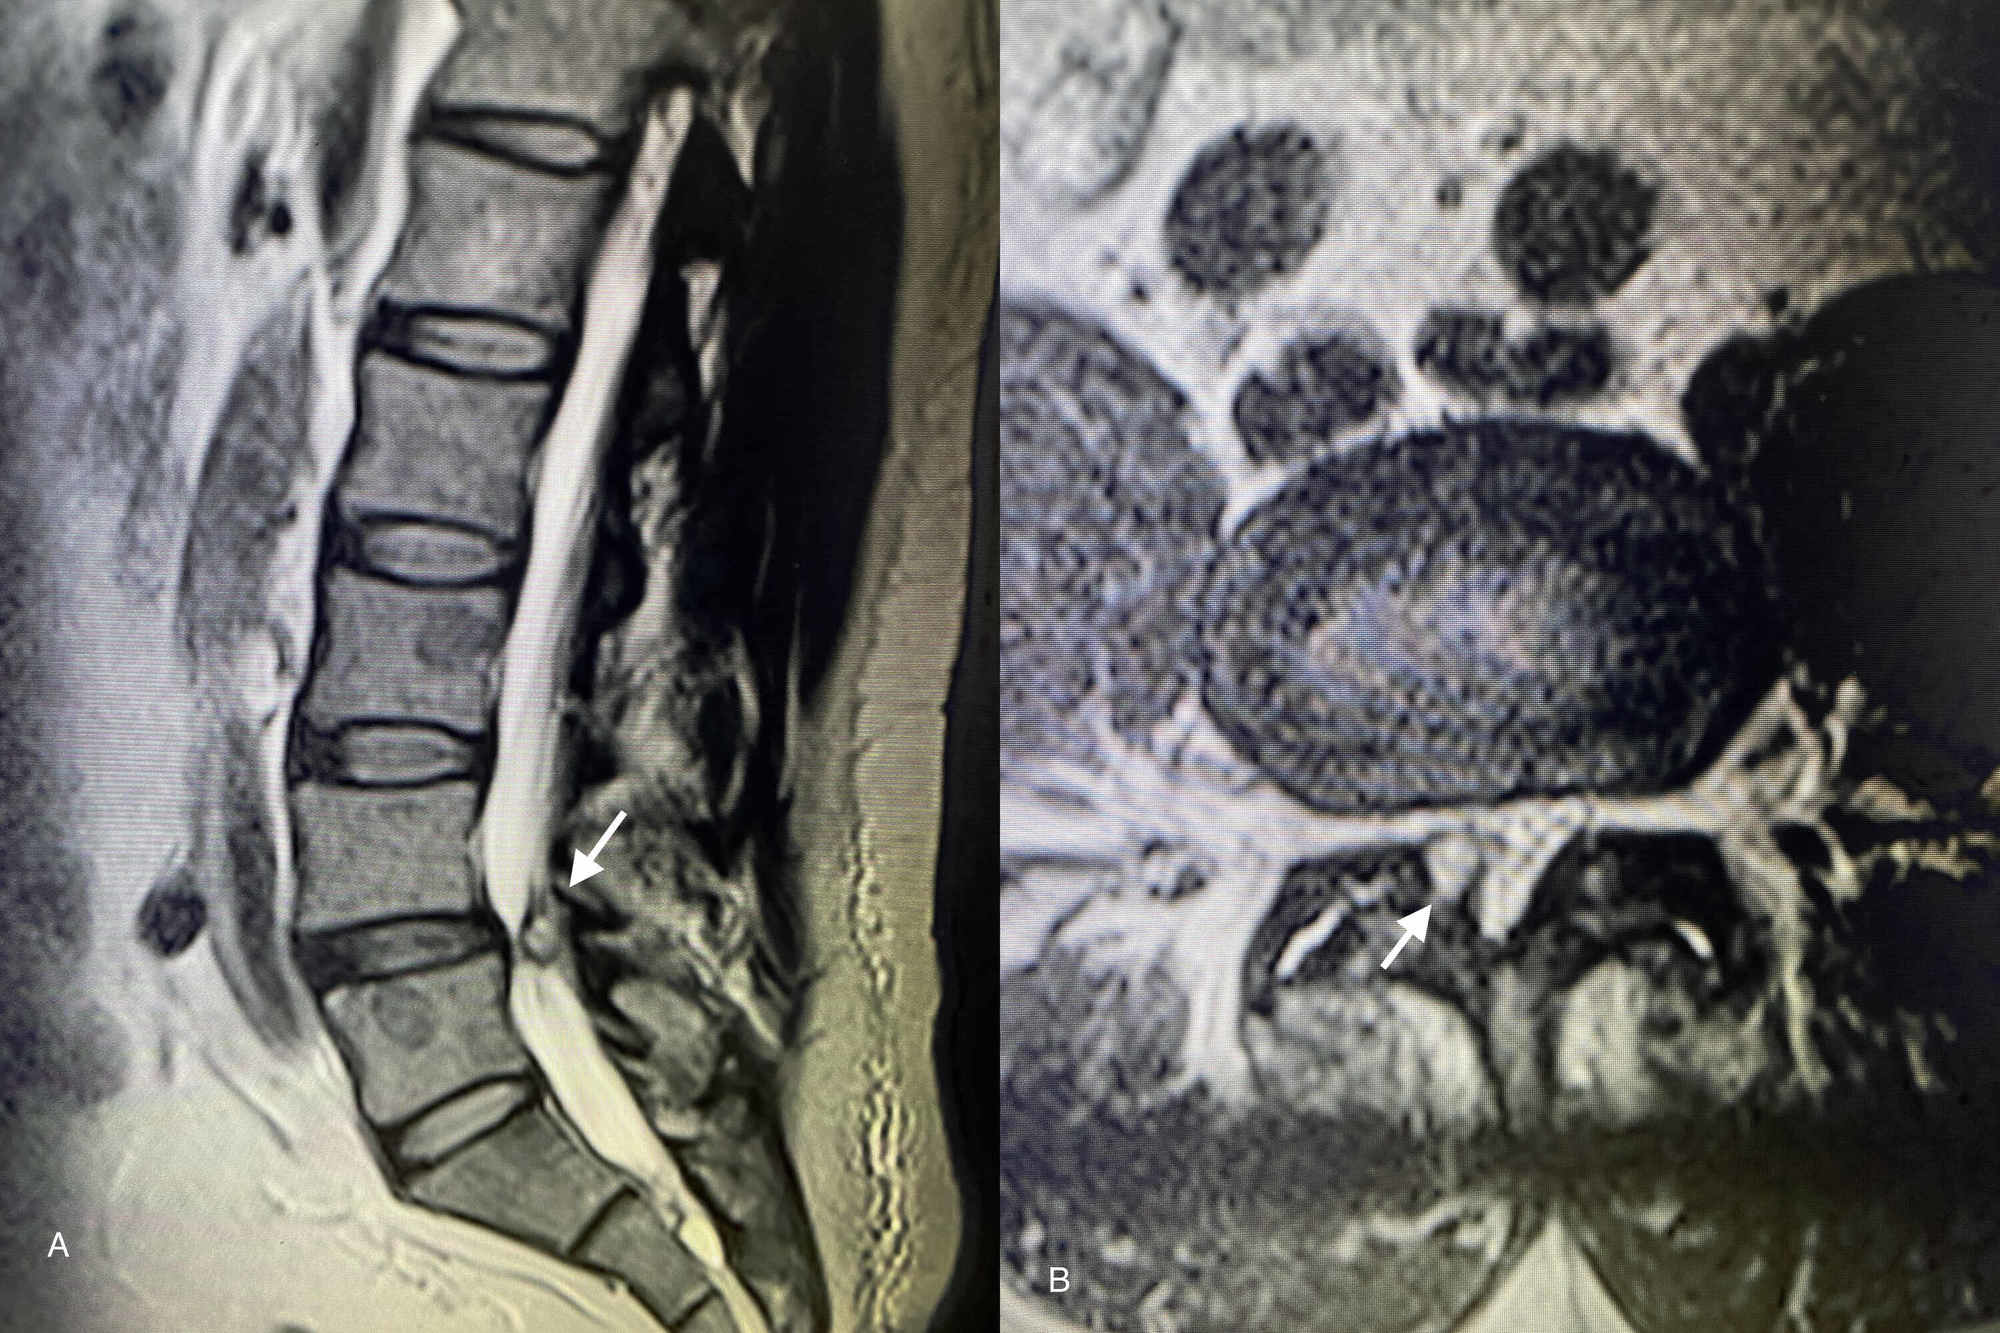

Synovial Facet Cyst Spine Orthobullets

Synovial Facet Cyst Spine Orthobullets Facet Joint Cyst Aspiration Cpt Code Standard documentation lists the facet joint to be blocked with hyphens. Facet joint interventions for pain management (a58477) for documentation. Currently, the facet joint injections procedural codes are located in the nervous system section of the cpt® manual. We have been seeing these more frequently and would like to know. Facet joint interventions for pain management. Article revised and published. Facet Joint Cyst Aspiration Cpt Code.

Lumbar Spine Facet Joint Synovial Cyst Radiology Mri vrogue.co Facet Joint Cyst Aspiration Cpt Code Currently, the facet joint injections procedural codes are located in the nervous system section of the cpt® manual. How would you suggest coding facet joint aspirations? Facet joint interventions for pain management. Standard documentation lists the facet joint to be blocked with hyphens. Each facet joint = one. Article revised and published on 11/30/2023 effective for dates of service on. Facet Joint Cyst Aspiration Cpt Code.

Synovial Facet Cyst Spine Orthobullets Facet Joint Cyst Aspiration Cpt Code Standard documentation lists the facet joint to be blocked with hyphens. Currently, the facet joint injections procedural codes are located in the nervous system section of the cpt® manual. Each facet joint = one. Use this page to view details for the local coverage article for billing and coding: Facet joint interventions for pain management (a58477) for documentation. How would. Facet Joint Cyst Aspiration Cpt Code.